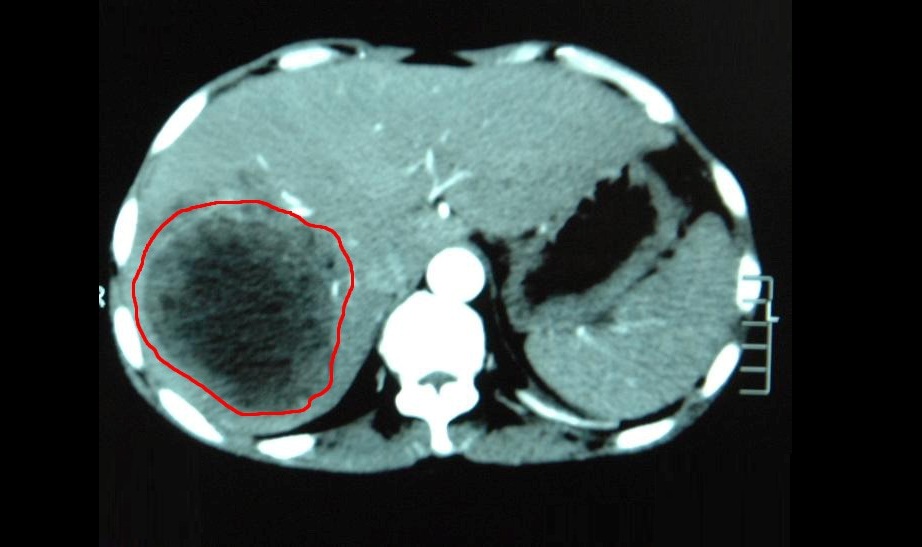

Компьютерная томография печени позволяет специалистам получить детализированное представление о состоянии органа. На полученных изображениях чётко видны очертания печени, её объём, плотность тканей, а также возможные отклонения – кисты, новообразования, отложения кальция, зоны воспаления или жировой инфильтрации. Высокая точность метода делает возможным обнаружение изменений даже в глубоко расположенных участках, а также позволяет проследить, затронуты ли близлежащие анатомические структуры, включая желчный пузырь, поджелудочную железу, желудок и крупные сосудистые стволы.

Особую ценность КТ имеет при диагностике очаговых образований. Метод помогает определить точные размеры и расположение опухоли, оценить её плотность, связь с сосудистыми структурами и другими анатомическими элементами. Также можно отличить доброкачественное образование от злокачественного по ряду характерных признаков, хотя окончательное заключение всегда требует гистологического подтверждения. При подозрении на метастазы из других органов КТ печени используется как метод скрининга и позволяет отследить множественные очаги поражения.